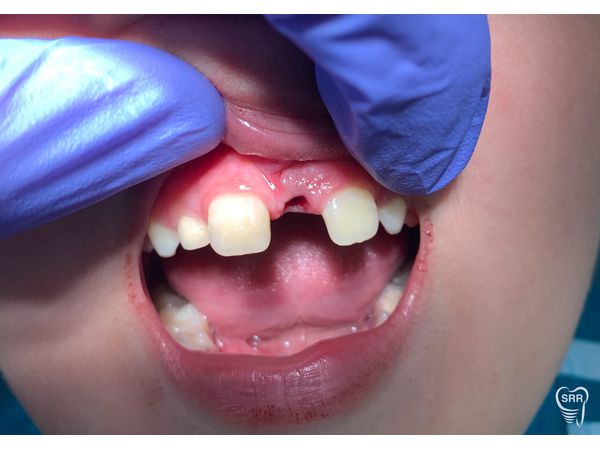

Сверхкомплектный 21-й зуб бочкообразной формы располагался между резцами верхней челюсти, имел два бугра. Реакция на холод и простукивание безболезненная.

K00.10 Сверхкомплектный 21-й зуб в области резцов (мезиодентия).

Пациенту удалили аномальный зуб под инфильтрационной анестезией раствором Ультракаин Д-С (1,7 мл), после чего осмотрели лунку: она заполнилась сгустком крови, края сжались.